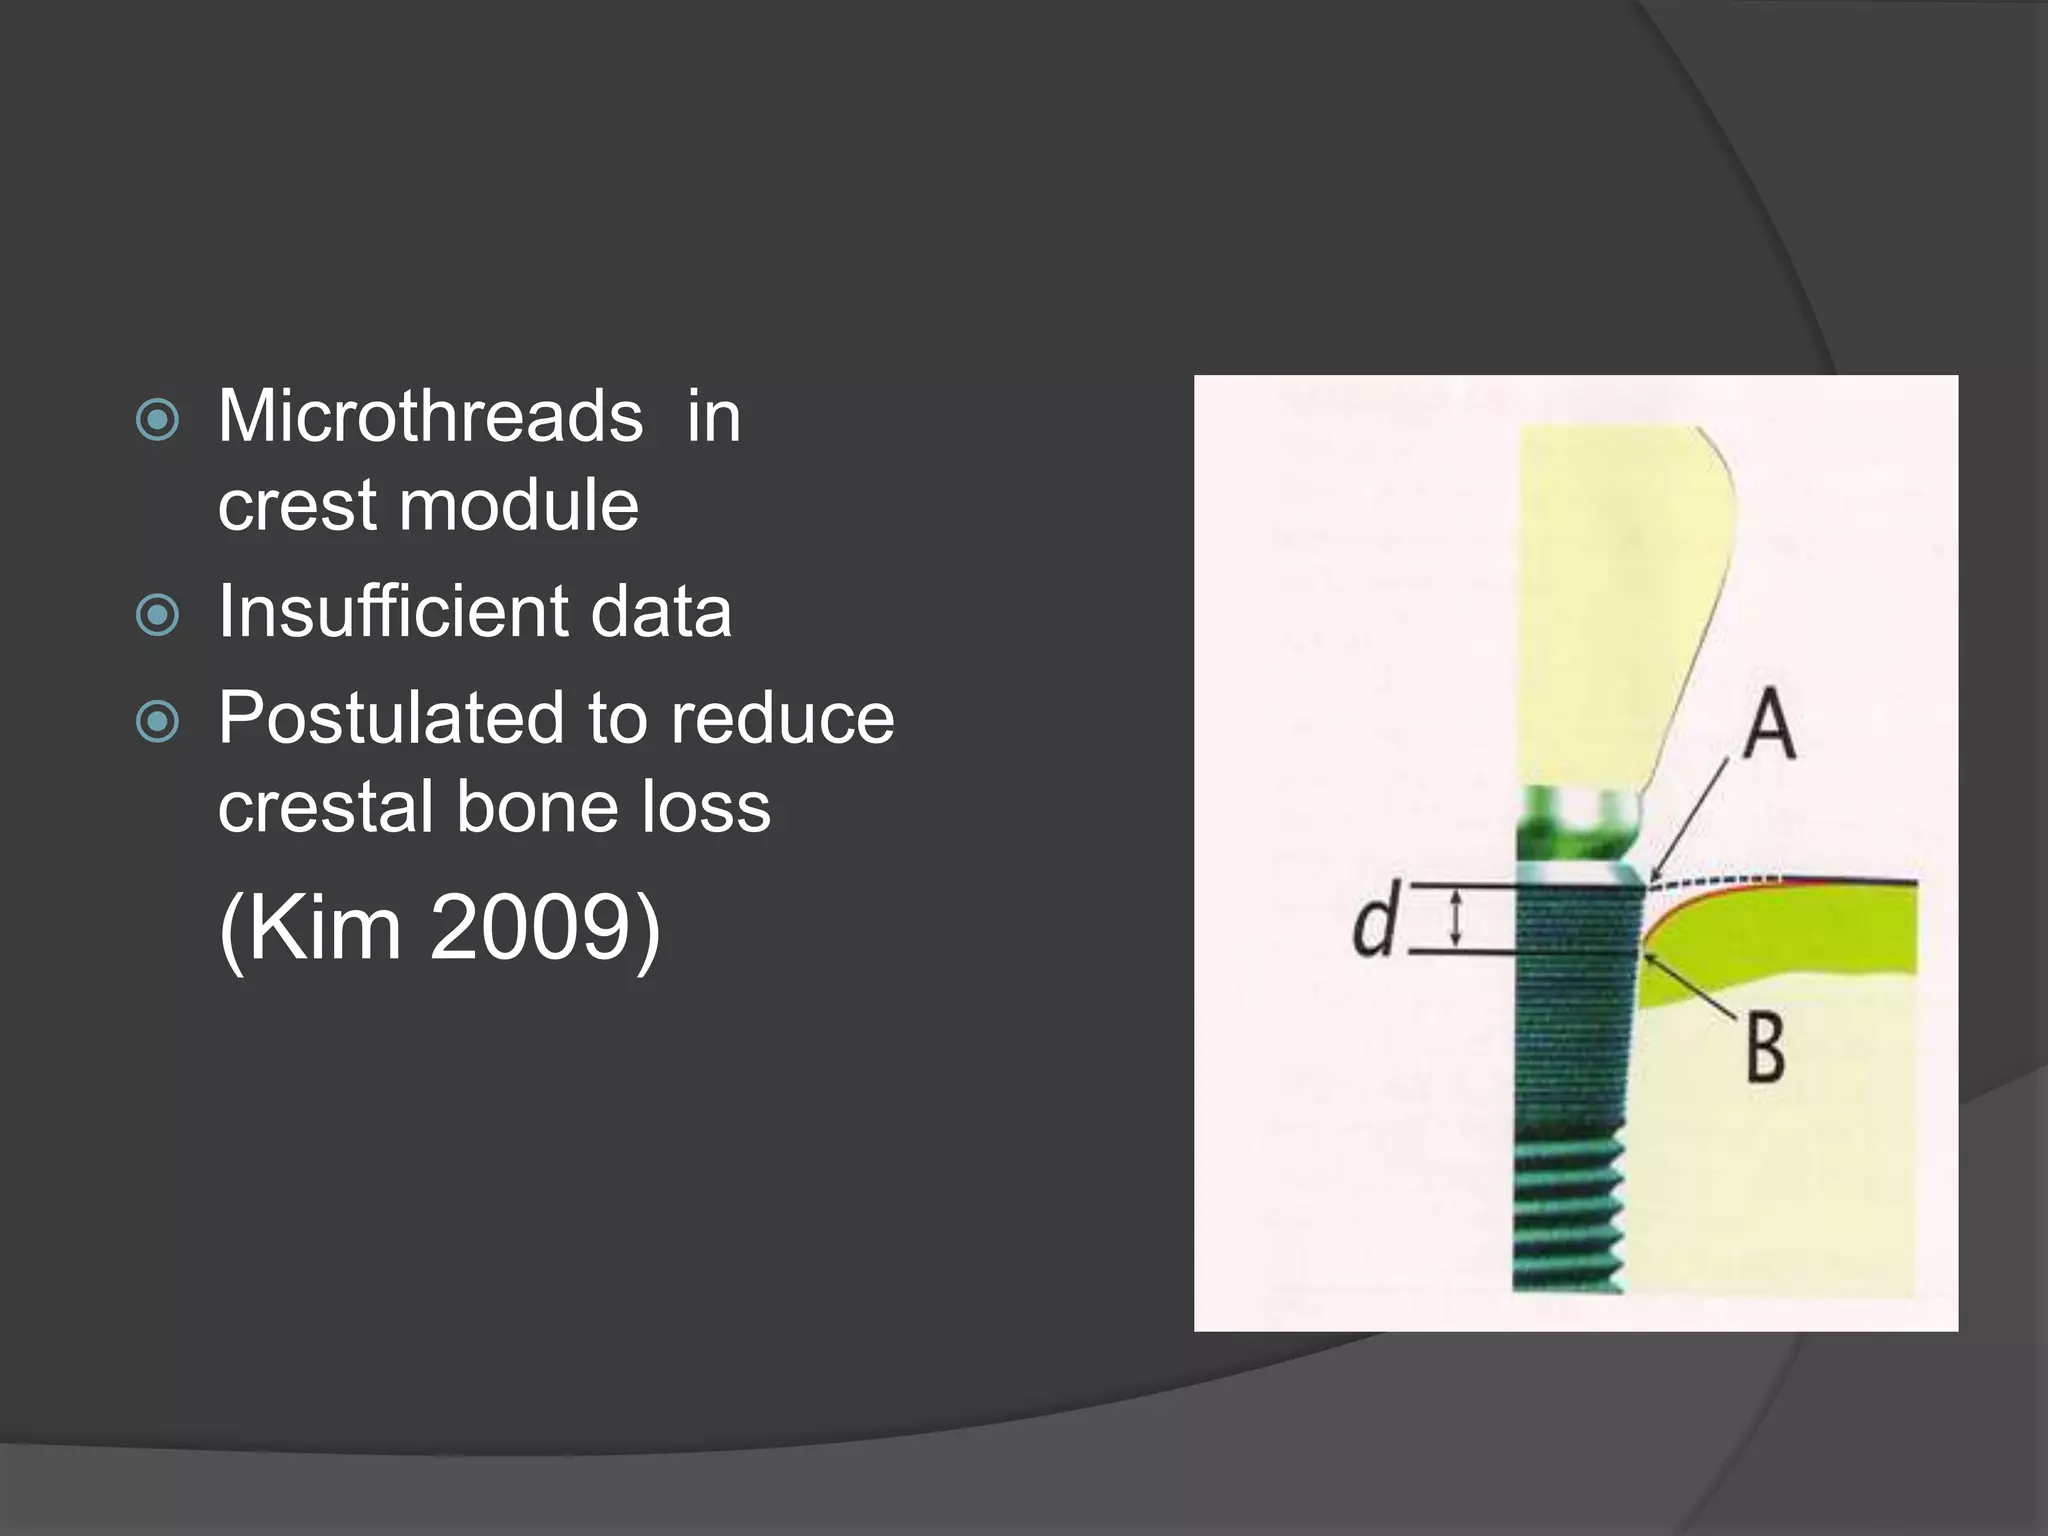

This document discusses factors that influence osseointegration and primary stability of dental implants, including implant design characteristics, surgical technique, and loading protocols. Specifically, it covers the processes of osseointegration and how forces on implants can either promote or inhibit bone remodeling. Key implant design considerations like length, diameter, threads, coatings and surface topography are analyzed in terms of their effects on stress distribution and bone-implant contact. The importance of primary stability and factors influencing it like bone quality and surgical skill are also addressed. Loading protocols ranging from immediate to conventional loading are compared.